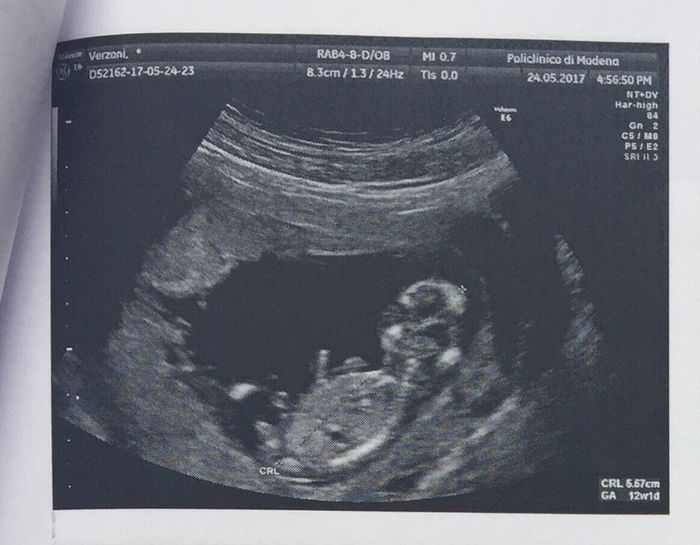

Eco translucenza... perfetta 😍😇

Ed ecco il nostro fagiolino/a... di pancia e di schiena ☺️😉 13 cm di puro amore!!!

Ciao, il CRL dice 6.28 quindi significa che dal cranio all'osso sacro misura così.. poi ci dovresti aggiungere le gambe che ovviamente non vengono misurate ma saranno circa altri 2/3cm più o meno (indicativamente poco meno della metà del corpo).. non voglio smontarti assolutamente ma 13 cm alle tue settimane è davvero tanto.. sarebbe praticamente il doppio.. cmq augurissimi 🤗🤗🤗

In realtà sull'ecografia c'è scritto CRL , che è La lunghezza dalla testina al culetto (si misura cosi la lunghezza i primi periodi), 6,28 cm ....

Il mio alla translucenza fatta a 11+6 di CRL era 5.57 cm e la ginecologa ha anche detto che era più grande di 3 giorni..🤔